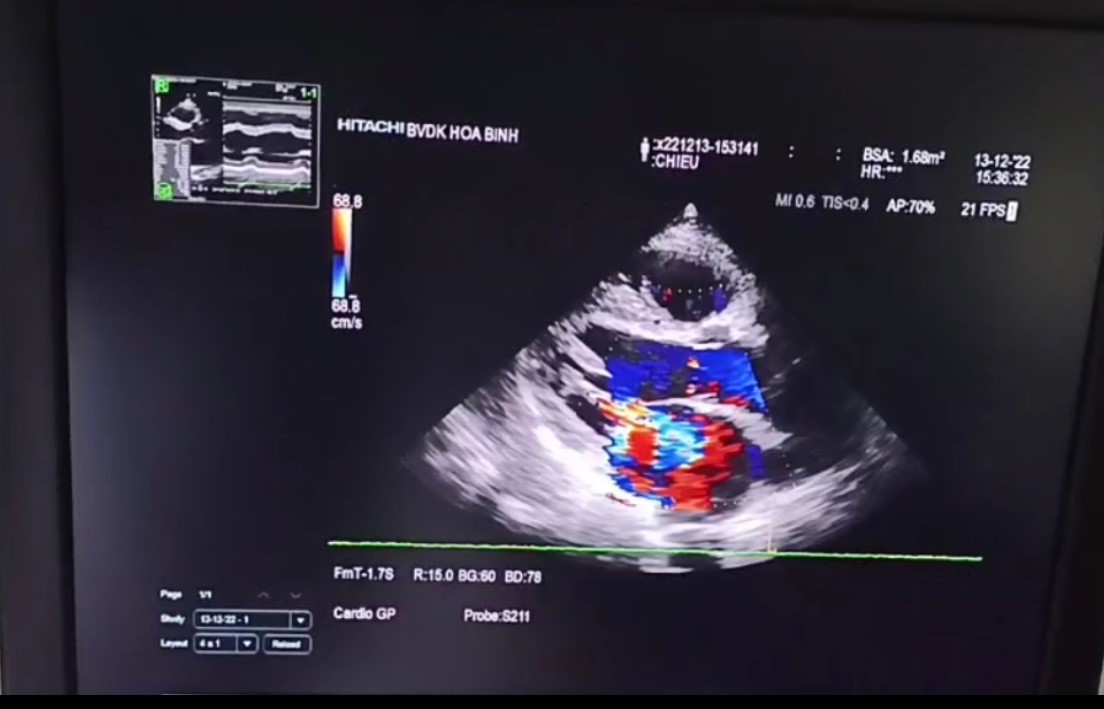

Hình ảnh siêu âm tim phát hiện bệnh nhân bị hẹp - hở van hai lá trong quá trình đi khám sức khoẻ định kỳ

Các chuyên gia Tim mạch, Bệnh viện Đa khoa tỉnh cho biết, van hai lá ngăn cách tâm nhĩ trái và tâm thất trái. Hẹp - hở van hai lá là tình trạng van không thể mở rộng trong thì tâm trương và đóng kín trong thì tâm thu như bình thường, gây ứ máu ở nhĩ trái. Lượng máu giàu oxy về tâm thất trái sẽ bị giảm sút, dẫn tới các mô và các cơ quan khác trong cơ thể không được nhận đủ oxy và các chất dinh dưỡng. Bệnh nếu không được phát hiện sớm sẽ rất nguy hiểm và có thể gây nhiều biến chứng ảnh hưởng đến sức khoẻ cũng như tính mạng người bệnh như suy tim, đột quỵ, rối loạn nhịp tim...